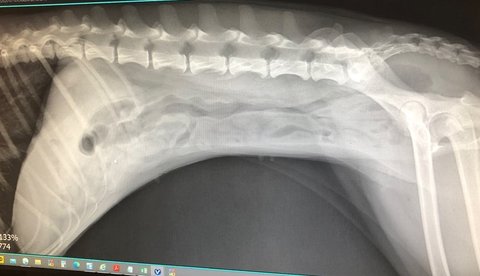

껌을 먹고 이틀이 지난 엑스레인데

대장이 울퉁불퉁하면 안되는데 울퉁불퉁한 상태이고,

대장 주위에 하얀게 다 염증, 십이지장 내강에 이물질이 있는 상태

초음파 및 엑스레이 결과 껌으로보이는 이물질이 많이 보여서 입원

엑스레이상 십이지장에 남아있다고 하고

계속되는 구토와 설사를 해서 도대체 얼마나 안녹으면 저럴까 하고